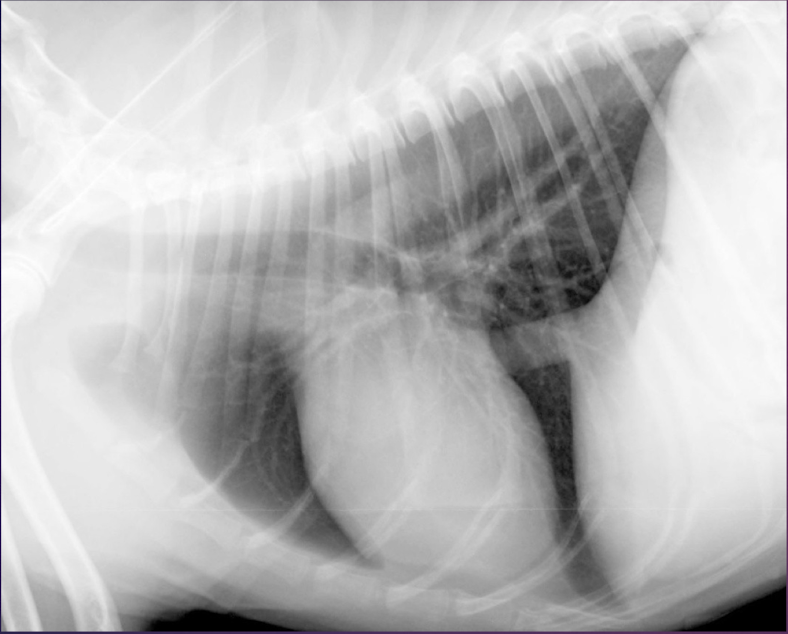

Right or left lateral?

Left